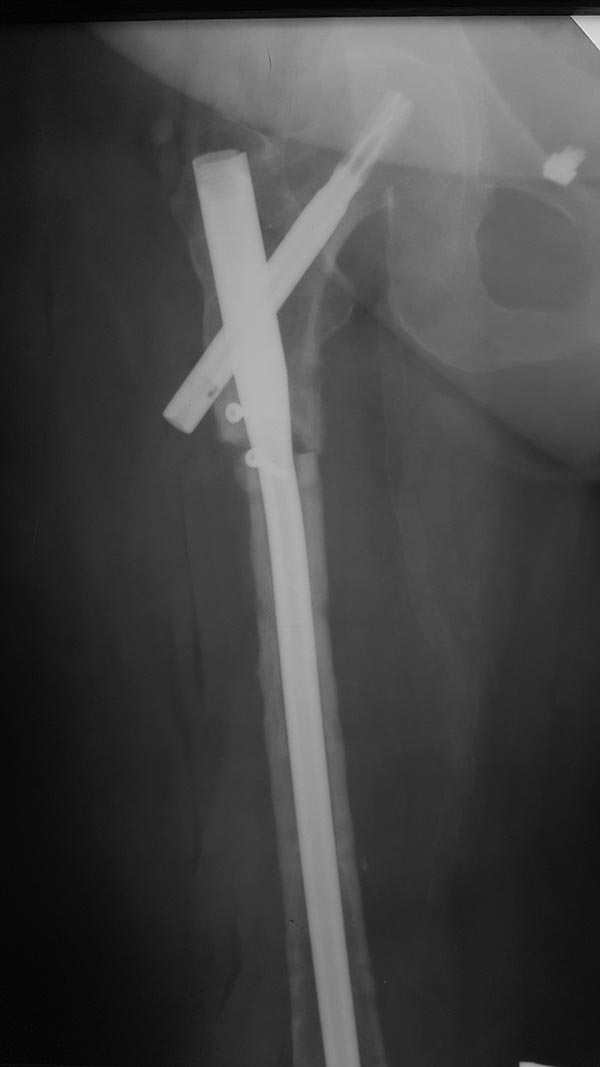

[Ortho] Атрофический псевдоартроз бедра

Операцию сделали, инфекции не выявлено, резецированы  концы бедренной

кости на 10 - 20 мм с каждой стороны, дистальный конец был

нежизнеспособен, щели перелома выполнены губчатым аутотрансплантантом,

также по передней поверхности  фиксирован винтами губчато-кортикальный

аутотрансплантант.